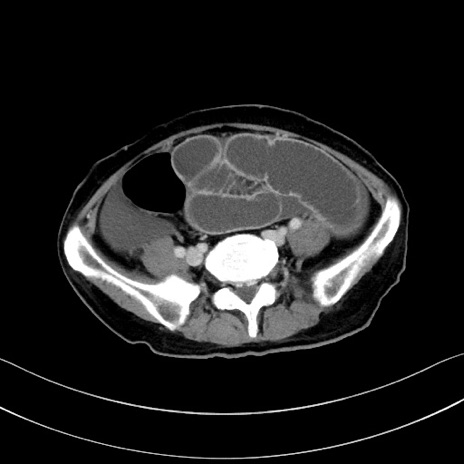

冠状断像